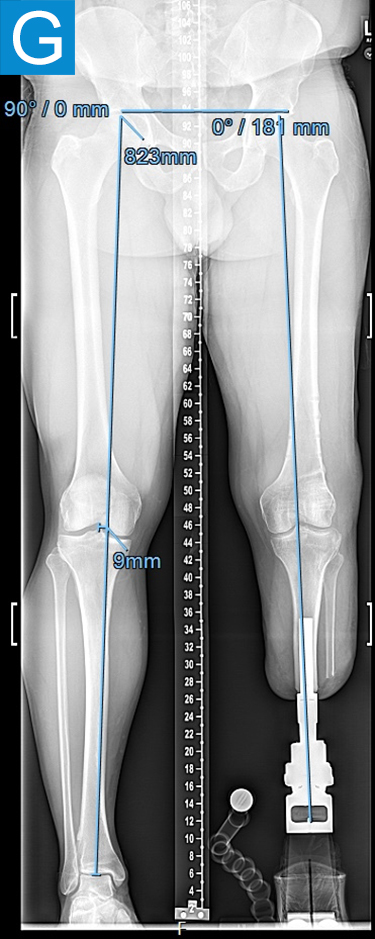

Figure 2. Postoperative clinical photos and radiographs. (A) Front and (B) rear views show the patient standing with the osseointegrated tibia prosthesis. (C) Photo shows stable and healthy skin at portal site to be, although slightly dry due to the winter weather. The gold-colored metal is part of the permanent transcutaneous implant; the shiny silver-colored metal beneath the gold is part of the clinician-removable prosthesis connector, and the matte silver metal beneath features a screw at the front, by which the patient secures the prosthesis. (D) Standing coronal radiograph depicts residual genu valgum in the osseointegrated leg. (E) Lateral radiograph of the osseointegrated tibia. (F) Coronal radiograph of the left knee shows the distal femur osteotomy. (G) Final coronal radiograph after distal femur plate and screw removal shows well-aligned left leg with osseointegrated prosthesis.